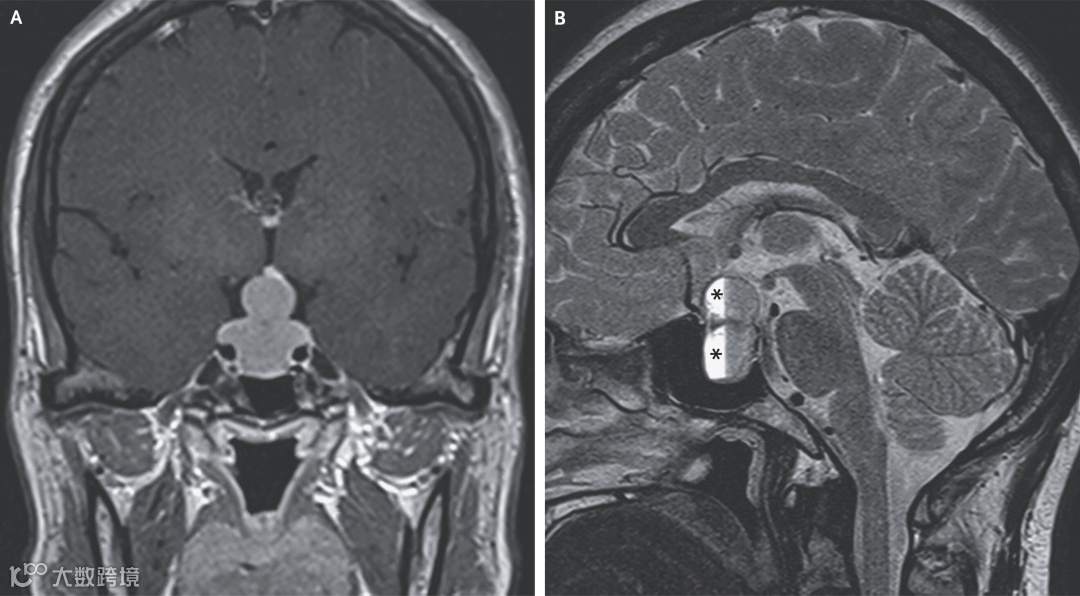

查体提示双眼视力均降至20/50,双眼视野与眼外肌运动正常。头部磁共振成像显示垂体腺体增大,自蝶鞍(颅底容纳垂体的凹陷)向鞍上池膨出,压迫视交叉,形成典型的“雪人征”(图A);同时可见垂体内出血(图B,星号)。所谓 “雪人征”,是指起源于蝶鞍内的缓慢生长肿瘤在向上生长过程中受鞍顶压迫而在中部出现 “勒痕” 样凹陷,从而呈现上下两团样外形。

实验室检查显示血清催乳素水平>200 mg/mL(参考范围3.3–26.7;按原文单位标注),并合并中枢性肾上腺功能不全与中枢性甲状腺功能减退。由此诊断为泌乳素分泌性垂体大腺瘤并亚临床型垂体卒中。